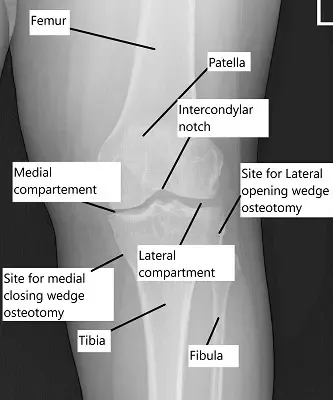

Radiografía que muestra la articulación de la rodilla

La osteotomía tibial alta puede clasificarse en:

Osteotomía de cuña de cierre lateral, donde se extrae una cuña de hueso.

Osteotomía de cuña de apertura medial, donde el hueso se abre y se sostiene con un injerto.

Ambos métodos dependen de placas y tornillos o fundiciones para la fijación.

Tipos y procedimiento:

- Cuña de cierre lateral: Se extrae una cuña predeterminada de hueso de la parte superior de la espinilla para corregir la alineación. Se pueden usar diferentes métodos, como fundiciones o plaques y tornillos, para fijar los extremos cortados entre sí.

- Cuña de apertura medial: Aquí se realiza un corte en la parte interna del hueso superior de la espinilla. El corte se abre y normalmente se rellena con un injerto óseo. De nuevo, puede arreglarse con una placa y tornillos.